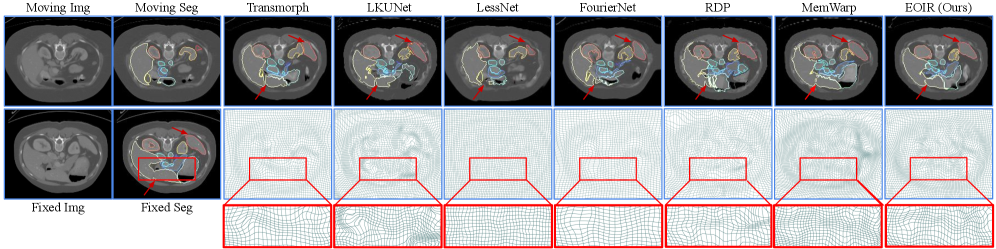

We demonstrate the capability of handling large deformations using inter-subject abdominal CT registration. As shown in Table I and Fig. 6, EOIR outperforms all other methods in registration accuracy without compromising smoothness. Specifically, EOIR surpasses the best conventional learning-based method, LKU-Net, by 14.87%, the best image pyramid-based method, MemWarp, by 0.65%, the best efficiency-driven method, FourierNet, by 41.66%, and the best discrete optimization-based method, SAMConvex, by 13.01%. It’s worth noting that while MemWarp matches EOIR in registration accuracy, it uses additive deformation composition, resulting in a less smooth field. Although FourierNet achieves a smoother field, it falls behind in registration accuracy. Both discrete optimization-based methods generate smooth deformation fields and improve upon efficiency-driven methods, but their registration accuracy lags behind all image pyramid-based methods and EOIR.

Refer to caption

Figure 6: Qualitative comparison on the abdomen CT dataset. TransMorph, LessNet, and FourierNet exhibit smooth deformation fields but fall short in anatomical alignment. MemWarp and LKUNet improve alignment but introduce more implausible voxels, while EOIR shows better accuracy-smoothness balance.